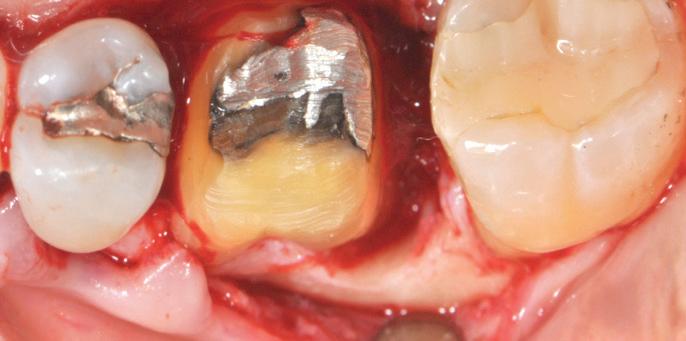

year old female patient presented with clinical and radiographic evidence of an mm.

The crown was biologically shaped and the root detoxified using Ellman burs. After flap opening and complete defect debridement, GEM S® was used to fill the defect.

The graft was then covered with Geistlich Bio-Gide®.

year old female patient presented with clinical and radiographic evidence of an mm

F l ap re fle c tio n sh o wing the d o n the dis t al o ≥ m m poc ket d epth